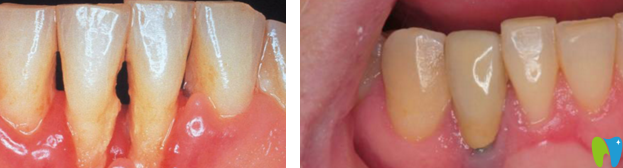

種植牙案例: